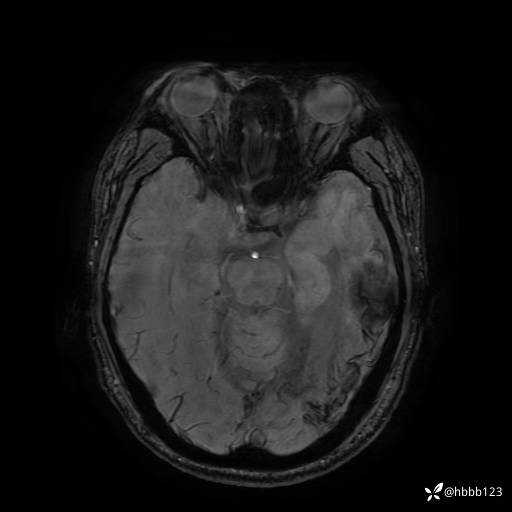

SWAN: